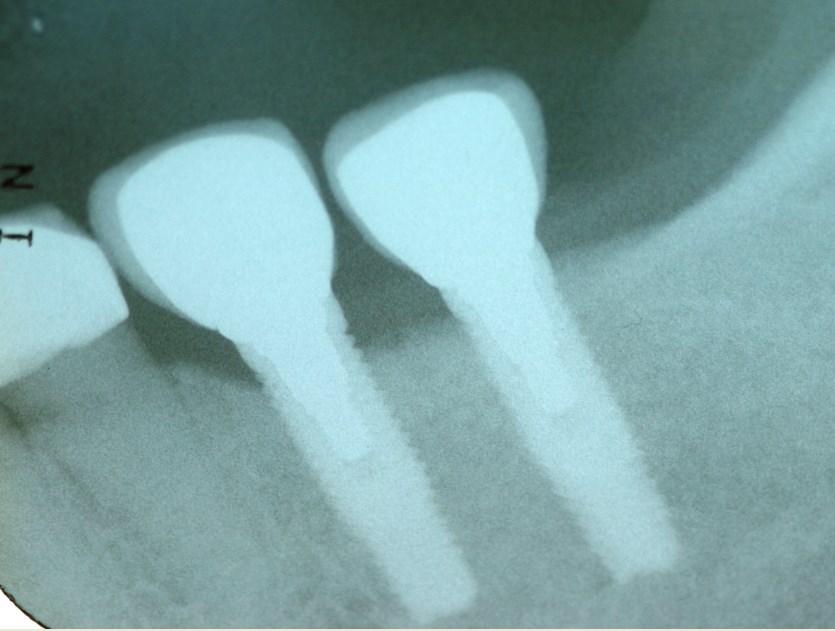

Έλλειψη δύο δοντιών κάτω αριστερά (γομφίων)

Αποκατάσταση της έλλειψης με εμφυτεύματα δοντιών

Ακτινογραφία των εμφυτευμάτων και των τεχνητών δοντιών